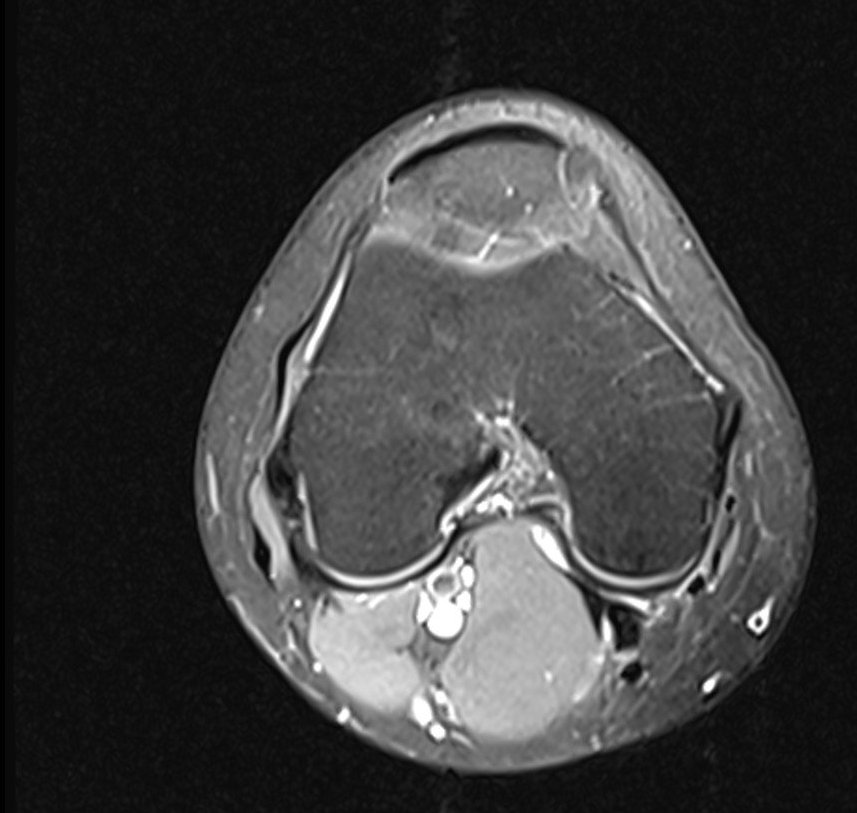

Здравейте, тъй като незнам как да ви кача целия диск Ви качвам малко снимки

Здравейте, благодаря за ЯМР-а.

Подборът на срезове/снимки не е най- добрият. Моля да изпратите диска на имейл: infо@beta-clinic.com или чрез спедитор на адреса на Бета клиник.